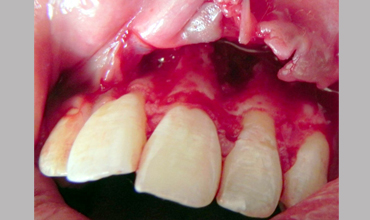

Surgical Management Of Large Periapical Cyst